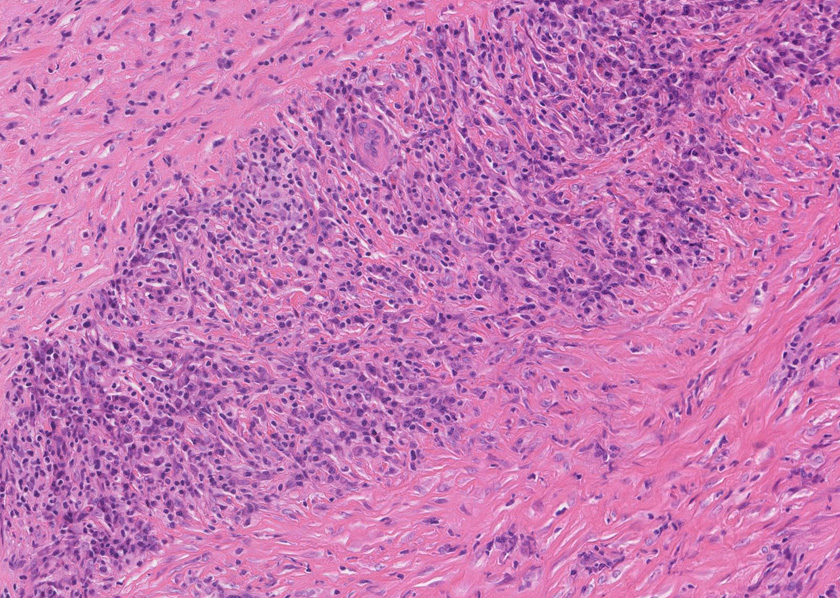

腹膜腫瘤の針生検組織片

組織像は膵腫瘤B, Cと同じくinflammatory myofibroblastic tumorである。島状に形質細胞主体の慢性炎症が強い。腹膜腫瘤には腺管は認められない。